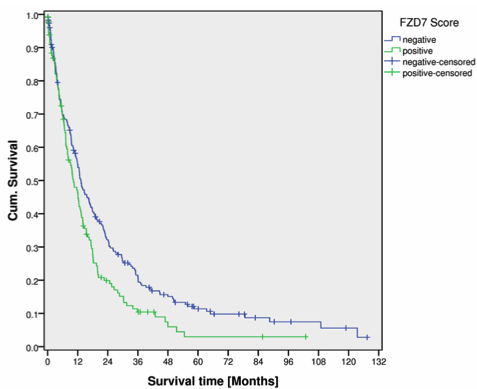

Transcriptional analyses demonstrated that SP cells express genes that encode for stem cell properties including FZD7, HEY1, SMO, and ADAM17. It was observed that ADAM17 and FZD7 are differentially expressed in human gastric cancer, and FZD7-positive cancers are associated with signifi- cantly shorter patient survival. In conclusion, human gastric cancer cell lines enclose a phenotypically and genotypically distinct cell population with tumor stem cell features. Phenotypic characteristics of this distinct cell population are also present in gastric cancer tissue, and correlate with patient survival.